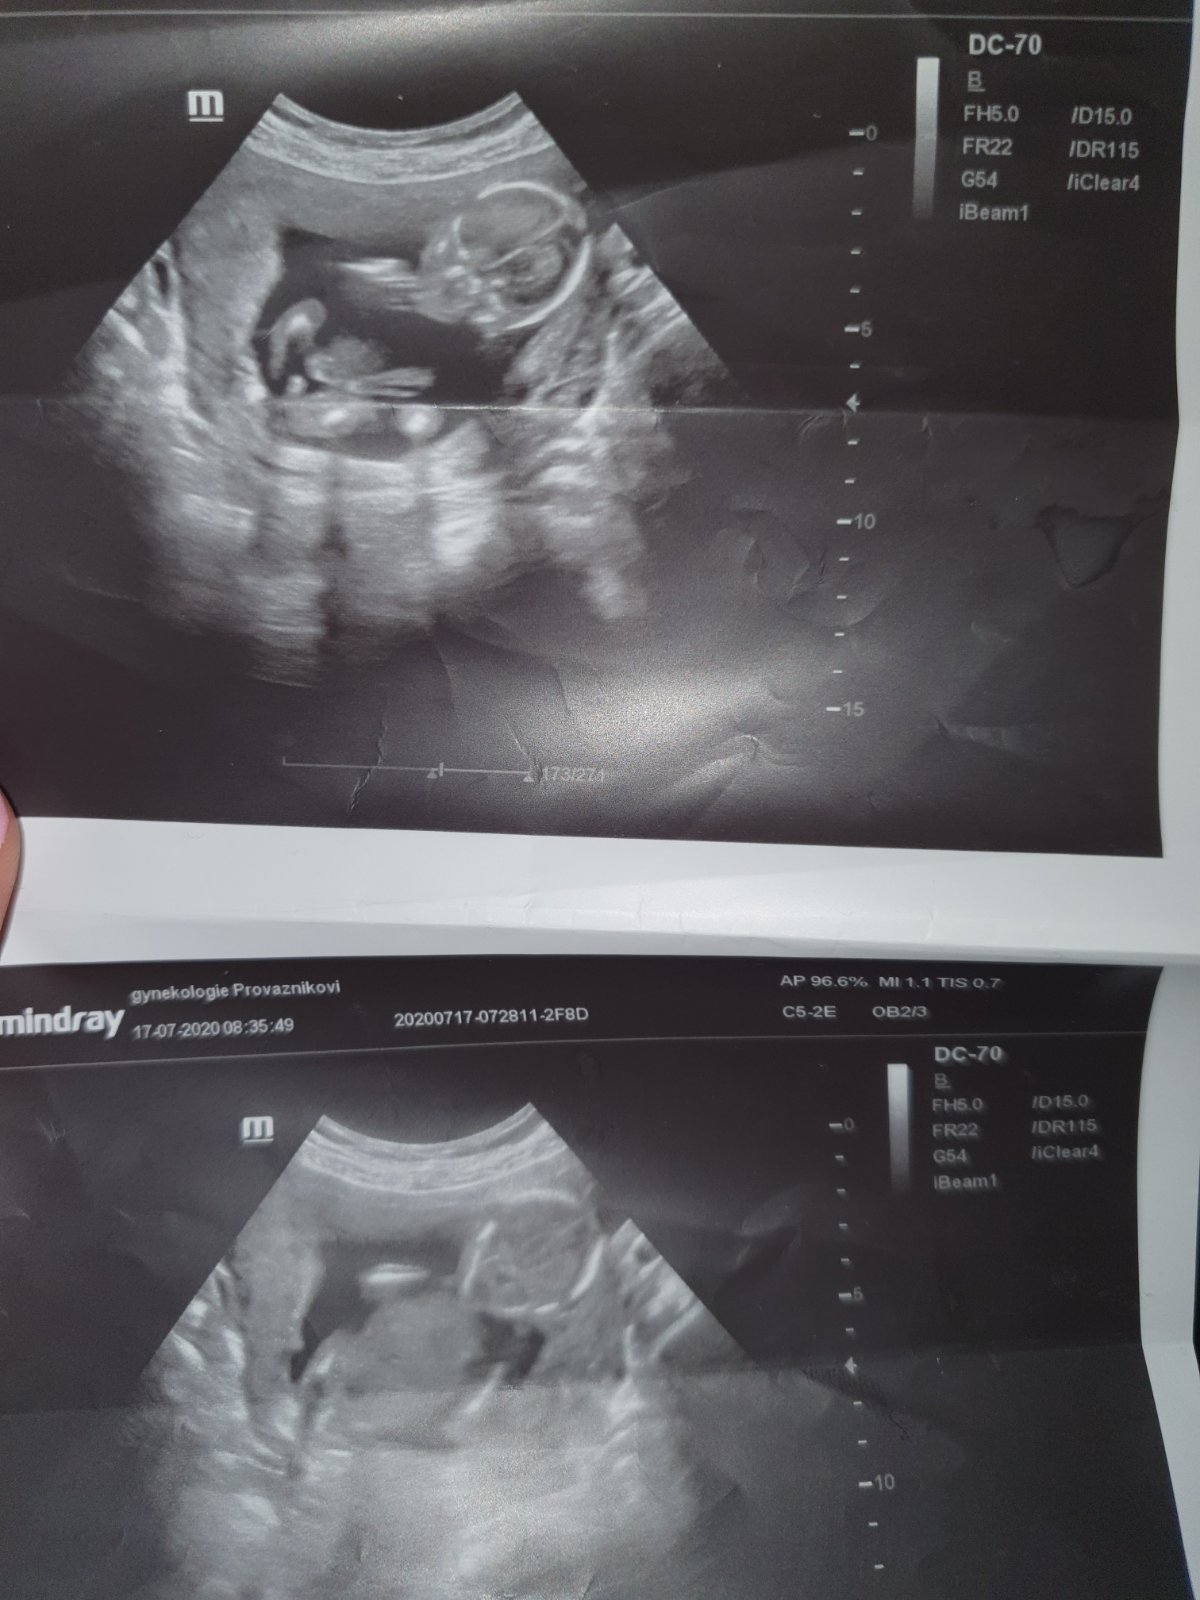

@allisenka no vim o čem mluvíš doma mam 9 let syna , pak 21nesicu syna a muz ma 5 let syna ted jsem v 18+5tt a přiložit foto cca ze 13tt a potom 15+6 . Foto ze 13tt tak me 76holek vi maminek reklo ze vidi holku kávové zrno a to tam vidím i ja a v 15+6tt me doktor rekl ze asi kluk a pritom u synu jsem jedla palive slané nevolnost jsem mela ze hrůza a ted jim sladké maso nemohu ani cítit a vse nasvědčuje na holcicku ale to co me doktor ukazuje na utz v 15+6 tt si myslíme ze je zkroucena noha pac takhle velký pindik neni možná okolo 20 tt😅🤣

@rennye spis me zajímá co si myslíte o te první fotce jak si doktor myslí že je to pindik nebo vam to taky neprijde spis jak ztocena noha

@almidrob2539 Pindík to není 😉

@rennye 😅🤣 at je to klidně kluk ale kdyz doktor rekne ze noha je pindik a ke všemu v 15+6tt a takhle veliký tak co me řekne na další kontrole to uz to bude mít jak slon 🤣😂🤣

@almidrob2539 mě se to taky nějak nezdá.. Že by mu levitoval ve vzduchu? 😃 Z té fotky to fakt nejde poznat. Ale je pravda, že u kluků jsem sama koukala, jake to je velké, když jsou takoví prtavi 😃